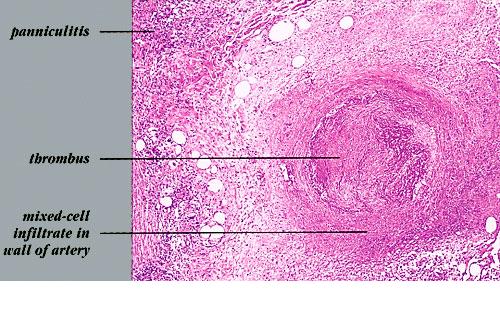

Nodular vasculitis = التهاب الاوعية العقيدي